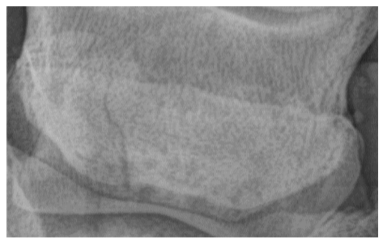

• what image is this?

dorsolateral palmar medial oblique